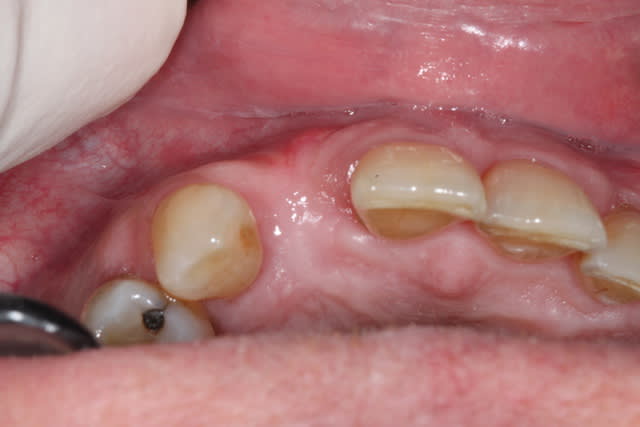

ici une extraction d'une 13 avec implantation de 14 et 13 direct.

14 pas beaucoup d'os en vestibulaire , donc expansion avec ostéotomes et ROG plus tard.

13 implantation dans une cavité+++, l'implant tient peu il baigne dans le bio-os.

il doit être recouvert d'une membrane (pour 14 surtout).

mais, j'ai de craintes de ne pas avoir suffisamment d'étanchéité.

c'est le cas, car une fois les sutures terminées, il me reste la membrane qui est exposée.